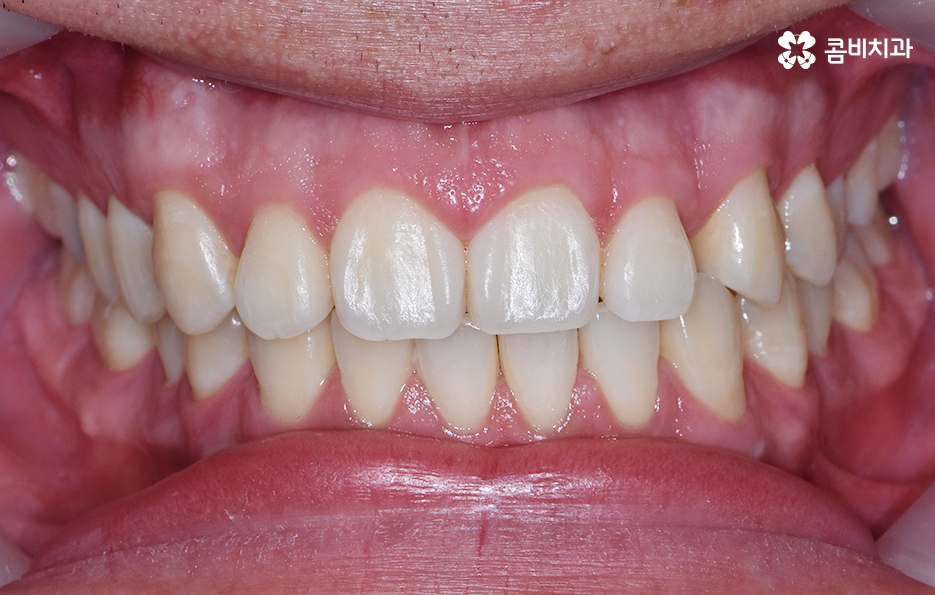

위 사례의 경우 앞니만 치아부분교정 통해서 치료가

이뤄진 사례로 치아의 돌출 여부나 골격, 교합 등을

고려하여 큰 문제 없이 치료가 가능했던 사례입니다.

치아부분교정은 위 사례와 같이 대부분 앞니 6개의 치아에

부분적으로 교정 장치를 부착하여 진행이 되며

전체 교정에 비해서 저렴하고 짧은 치료 기간이 장점입니다.

이물감이나 통증이 비교적 적다는 이점도 있으며